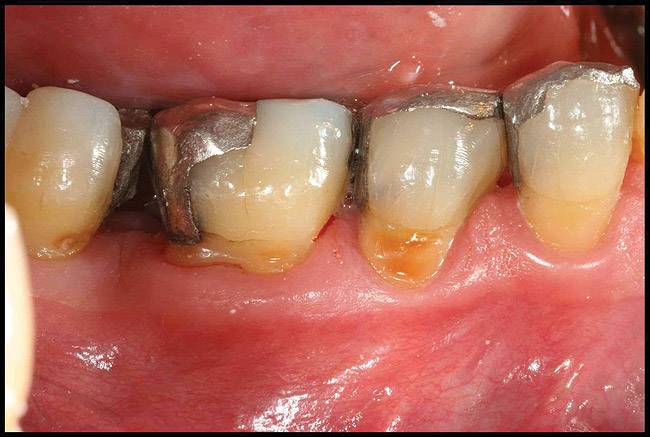

After complete management of moderate to severe periodontitis, including scaling and root planing and in some cases periodontal surgery, subsequent regular periodontal maintenance is reported to prevent tooth loss in up to 85% of patients over a long-term follow-up interval of up to 53 years.6,8 This high success rate of periodontal treatment is comparable to that of dental implants in replacing teeth lost to severe periodontal diseases, highlighting the predictability of maintaining the natural dentition in most patients with periodontal diseases9,10 (Figure 1A and Figure 1B).

Figure 1b  Long-term results of a case involving a 55-year-old woman treated by regenerative periodontal surgery followed by periodontal maintenance every 3 months for 8 years. (B) radiograph of the same area taken in July 2008.</a></span><P>Figure 1b</P></div>    <div class=